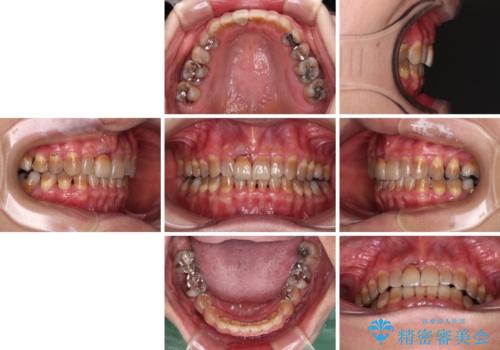

- 前歯のデコボコと、顎に負担のかかる歯並びを改善したいとのことで来院された患者様です。

うまく歯ぎしりができず、強く食いしばりをしてしまう咬み合わせであったため、奥歯に非常に負担がかかっていました。

インビザラインを用いて前歯のデコボコを改善するとともに、奥歯の咬み合わせを変えてスムーズに歯ぎしりできるように排列していくこととしました。

可能であれば上下正中を合わせ、左右の咬み合わせも改善したかったのですが、骨格的な左右差が大きかった上に、インビザラインでは限界があり、達成できませんでした。

それでも奥歯の負担を改善することができました。